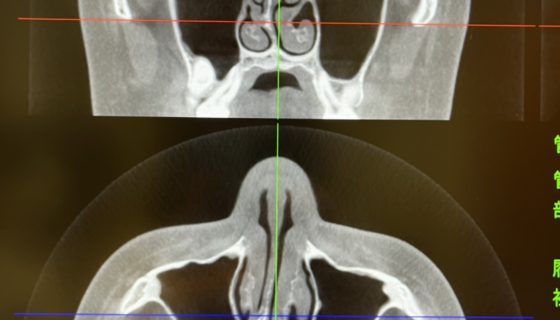

カテゴリー 日常 かすみがうら 投稿者 作成者: Kiyoshi 投稿日 2022/03/17 かすみがうら へのコメントはまだありません ここはいつも早くて日の出前に終わる。 華恋はずっと治らない鼻を 東京の医師を見つけ行ってみると 手術になった。 怖くてやらない医者が多いんだろうな。